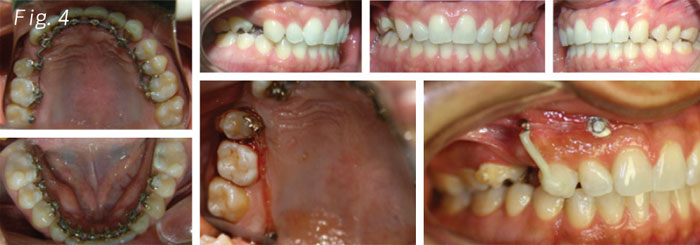

Continuing with the adjustments we found that it was impossible to move the second upper bicuspid (Fig.4). We placed two TADs, one of them applying direct pressure to the second upper bicuspid which had no positive results. We even tried making a little bit of luxation for movement, obtaining no results at all. On the other TAD we made a vertical movement on the upper right cuspid, applying a lever movement on the root (Fig. 4).

Making a close diagnosis on the right upper bicuspid area, we found a problem of hypercementosis on the second bicuspid. This forced us to make changes to the original treatment plan of placing an implant and taking a closer view. We had to work with the periodontics, prosthodontics and endodontics. Considering the mentioned outcomes, the decision of performing the root canal and building a flying bridge that would hold on to the second right upper bicuspid with the hypercementosis and leave a little extension to the cuspid, was taken (Fig. 5).